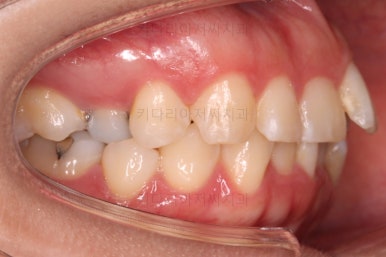

초진 시 입안의 모습입니다.

전반적으로 치열이 삐뚤고, 특정 앞니는 톡 튀어나가 미적으로 좋지 못한 상황이었습니다.

이갈이, 이악물기 습관도 있어서 앞니는 삐뚤어진 채로 치아가 많이 갈려있는 상황이었습니다.